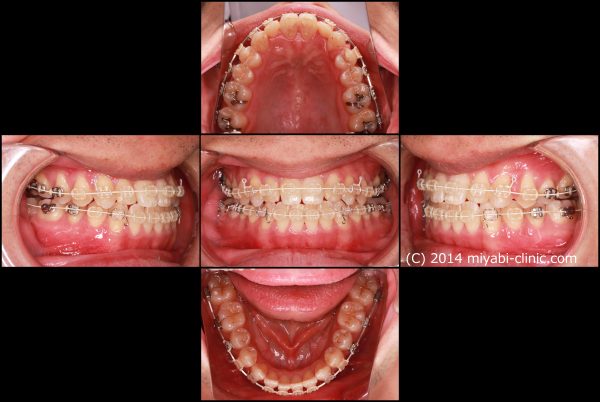

ワイヤーとゴムを使用した治療により反対咬合を修正しました。

2017年の6月27日にスタートして 2018年の10月2日に 終了 しました。

治療期間 16か月

上下の前歯が逆になっています。右上の犬歯は八重歯の状態です。

叢生を伴う 反対咬合(受け口)です。

小さい頃から受け口だったそうです。